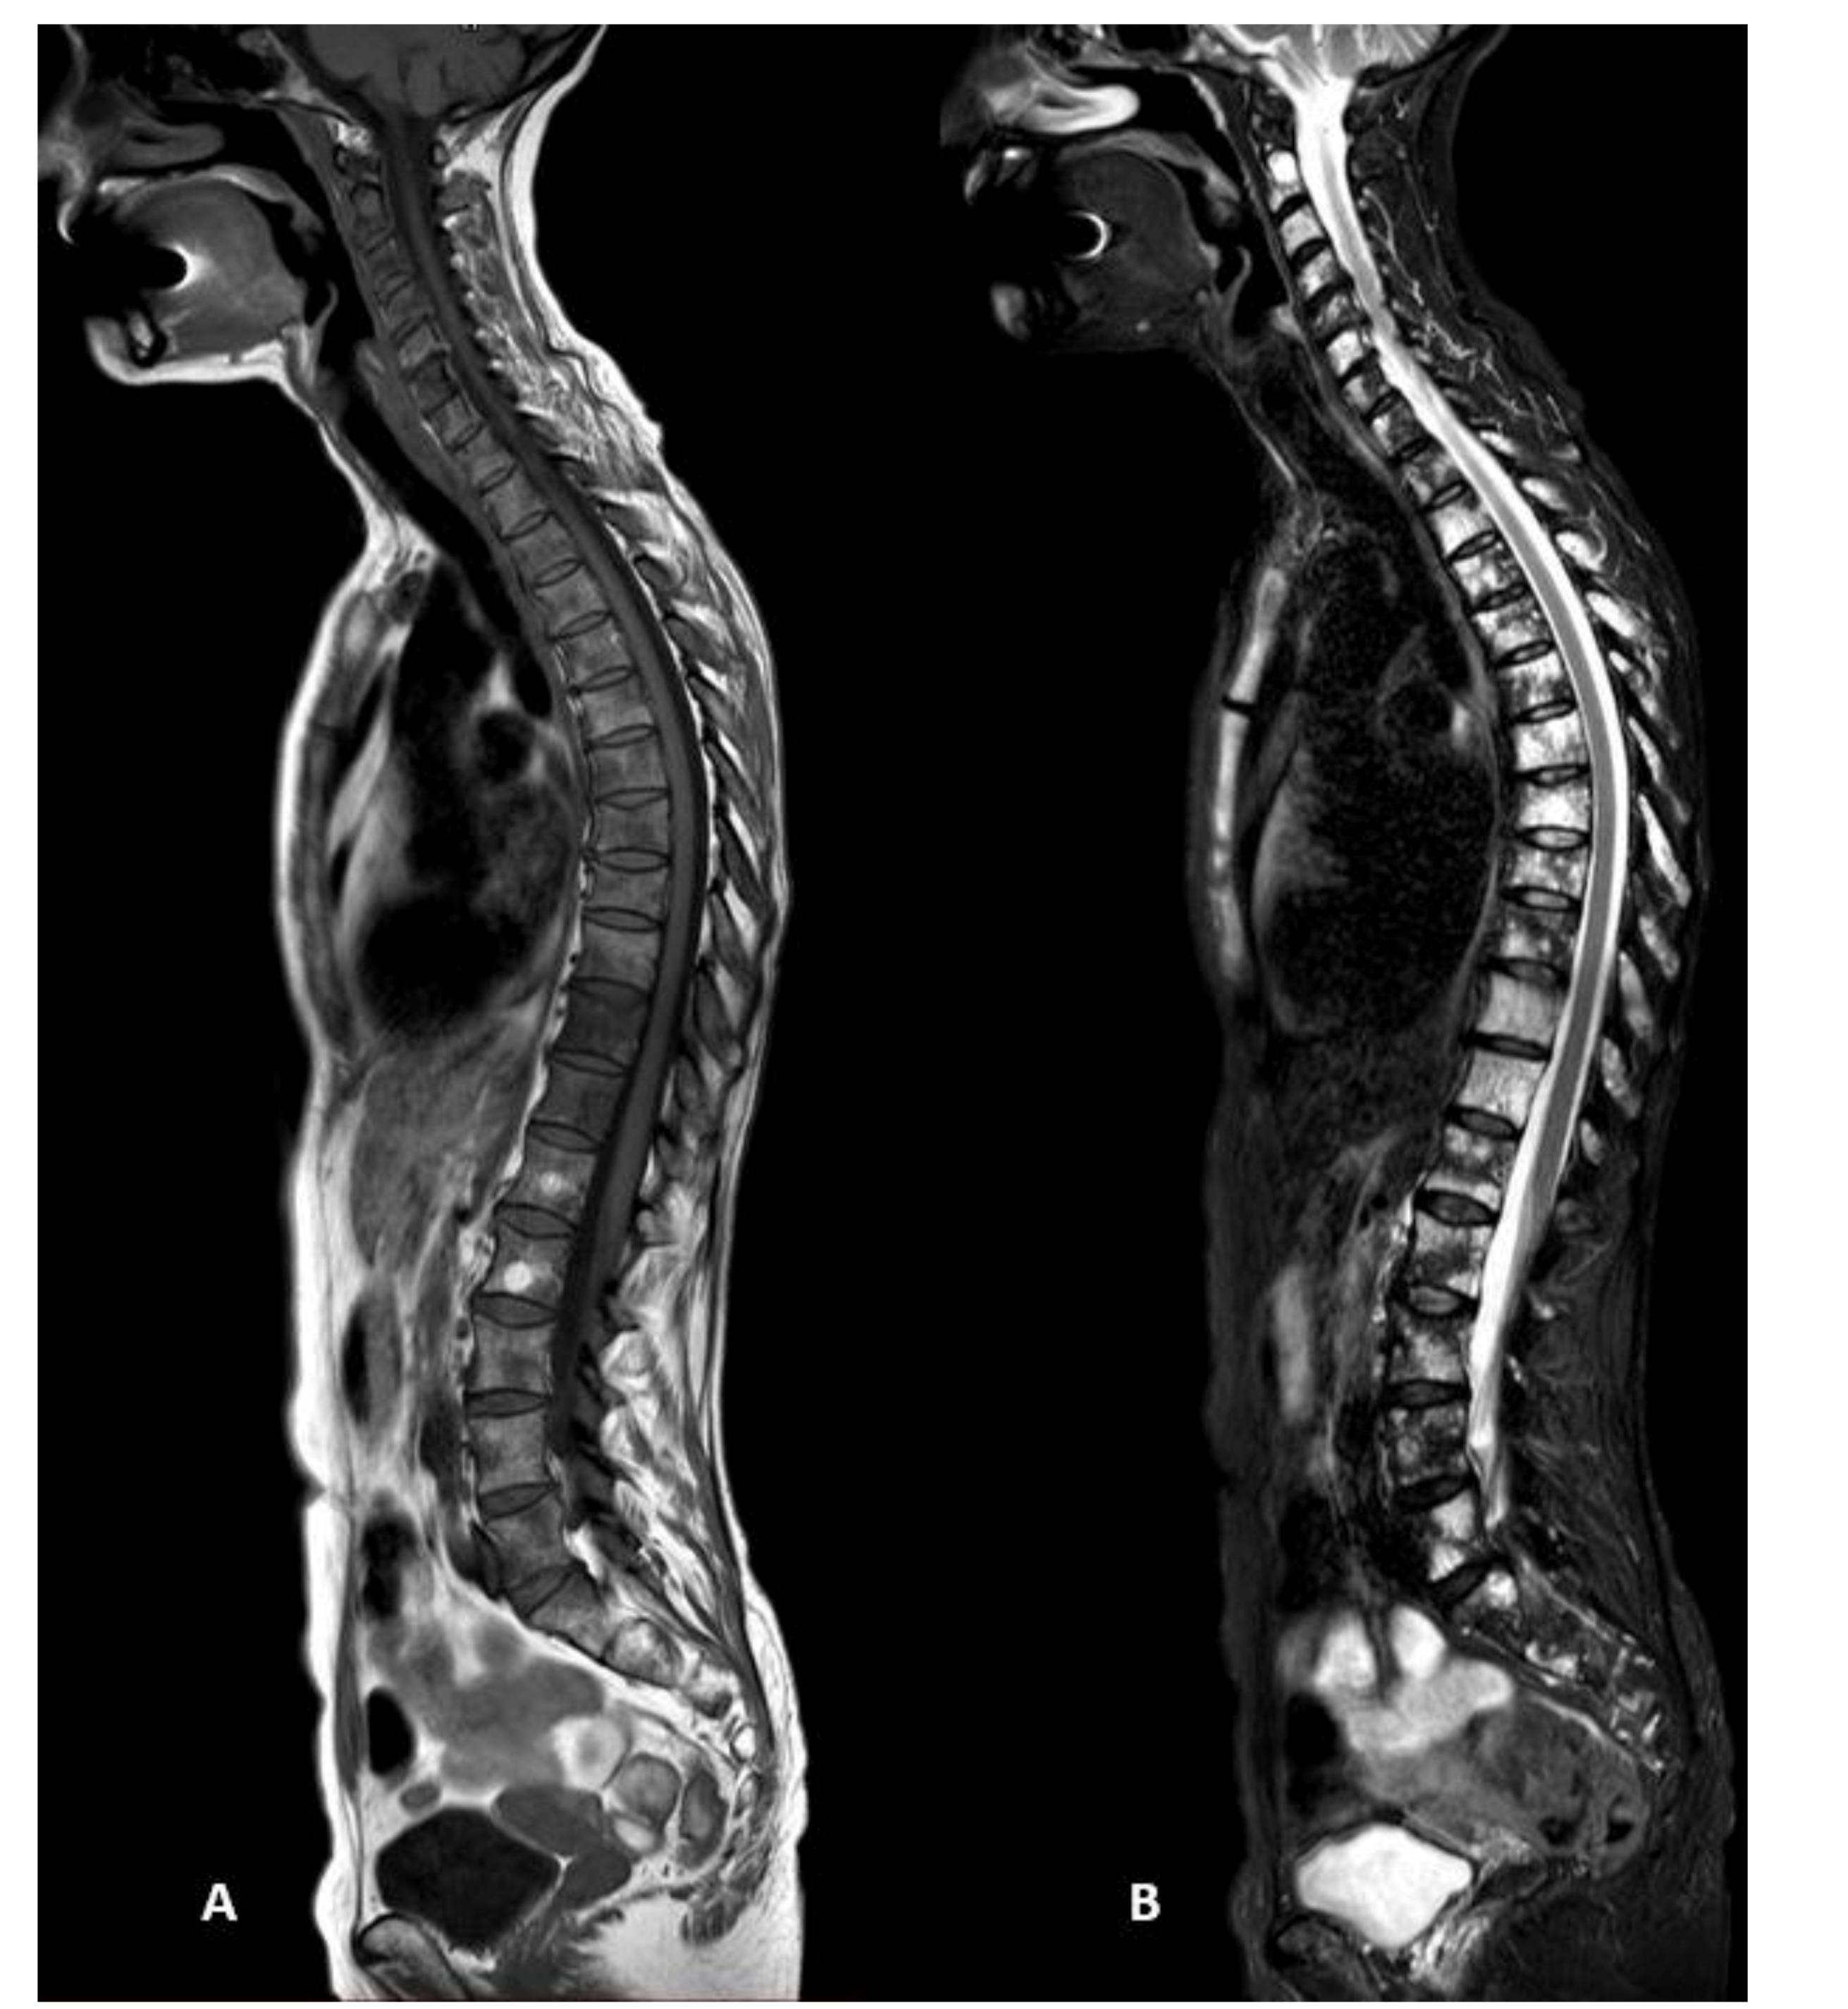

3.3. Radiological Pattern and Lesions’ Distribution

3.4. Standard vs. Short Protocols

2.1. WBMRI Protocol